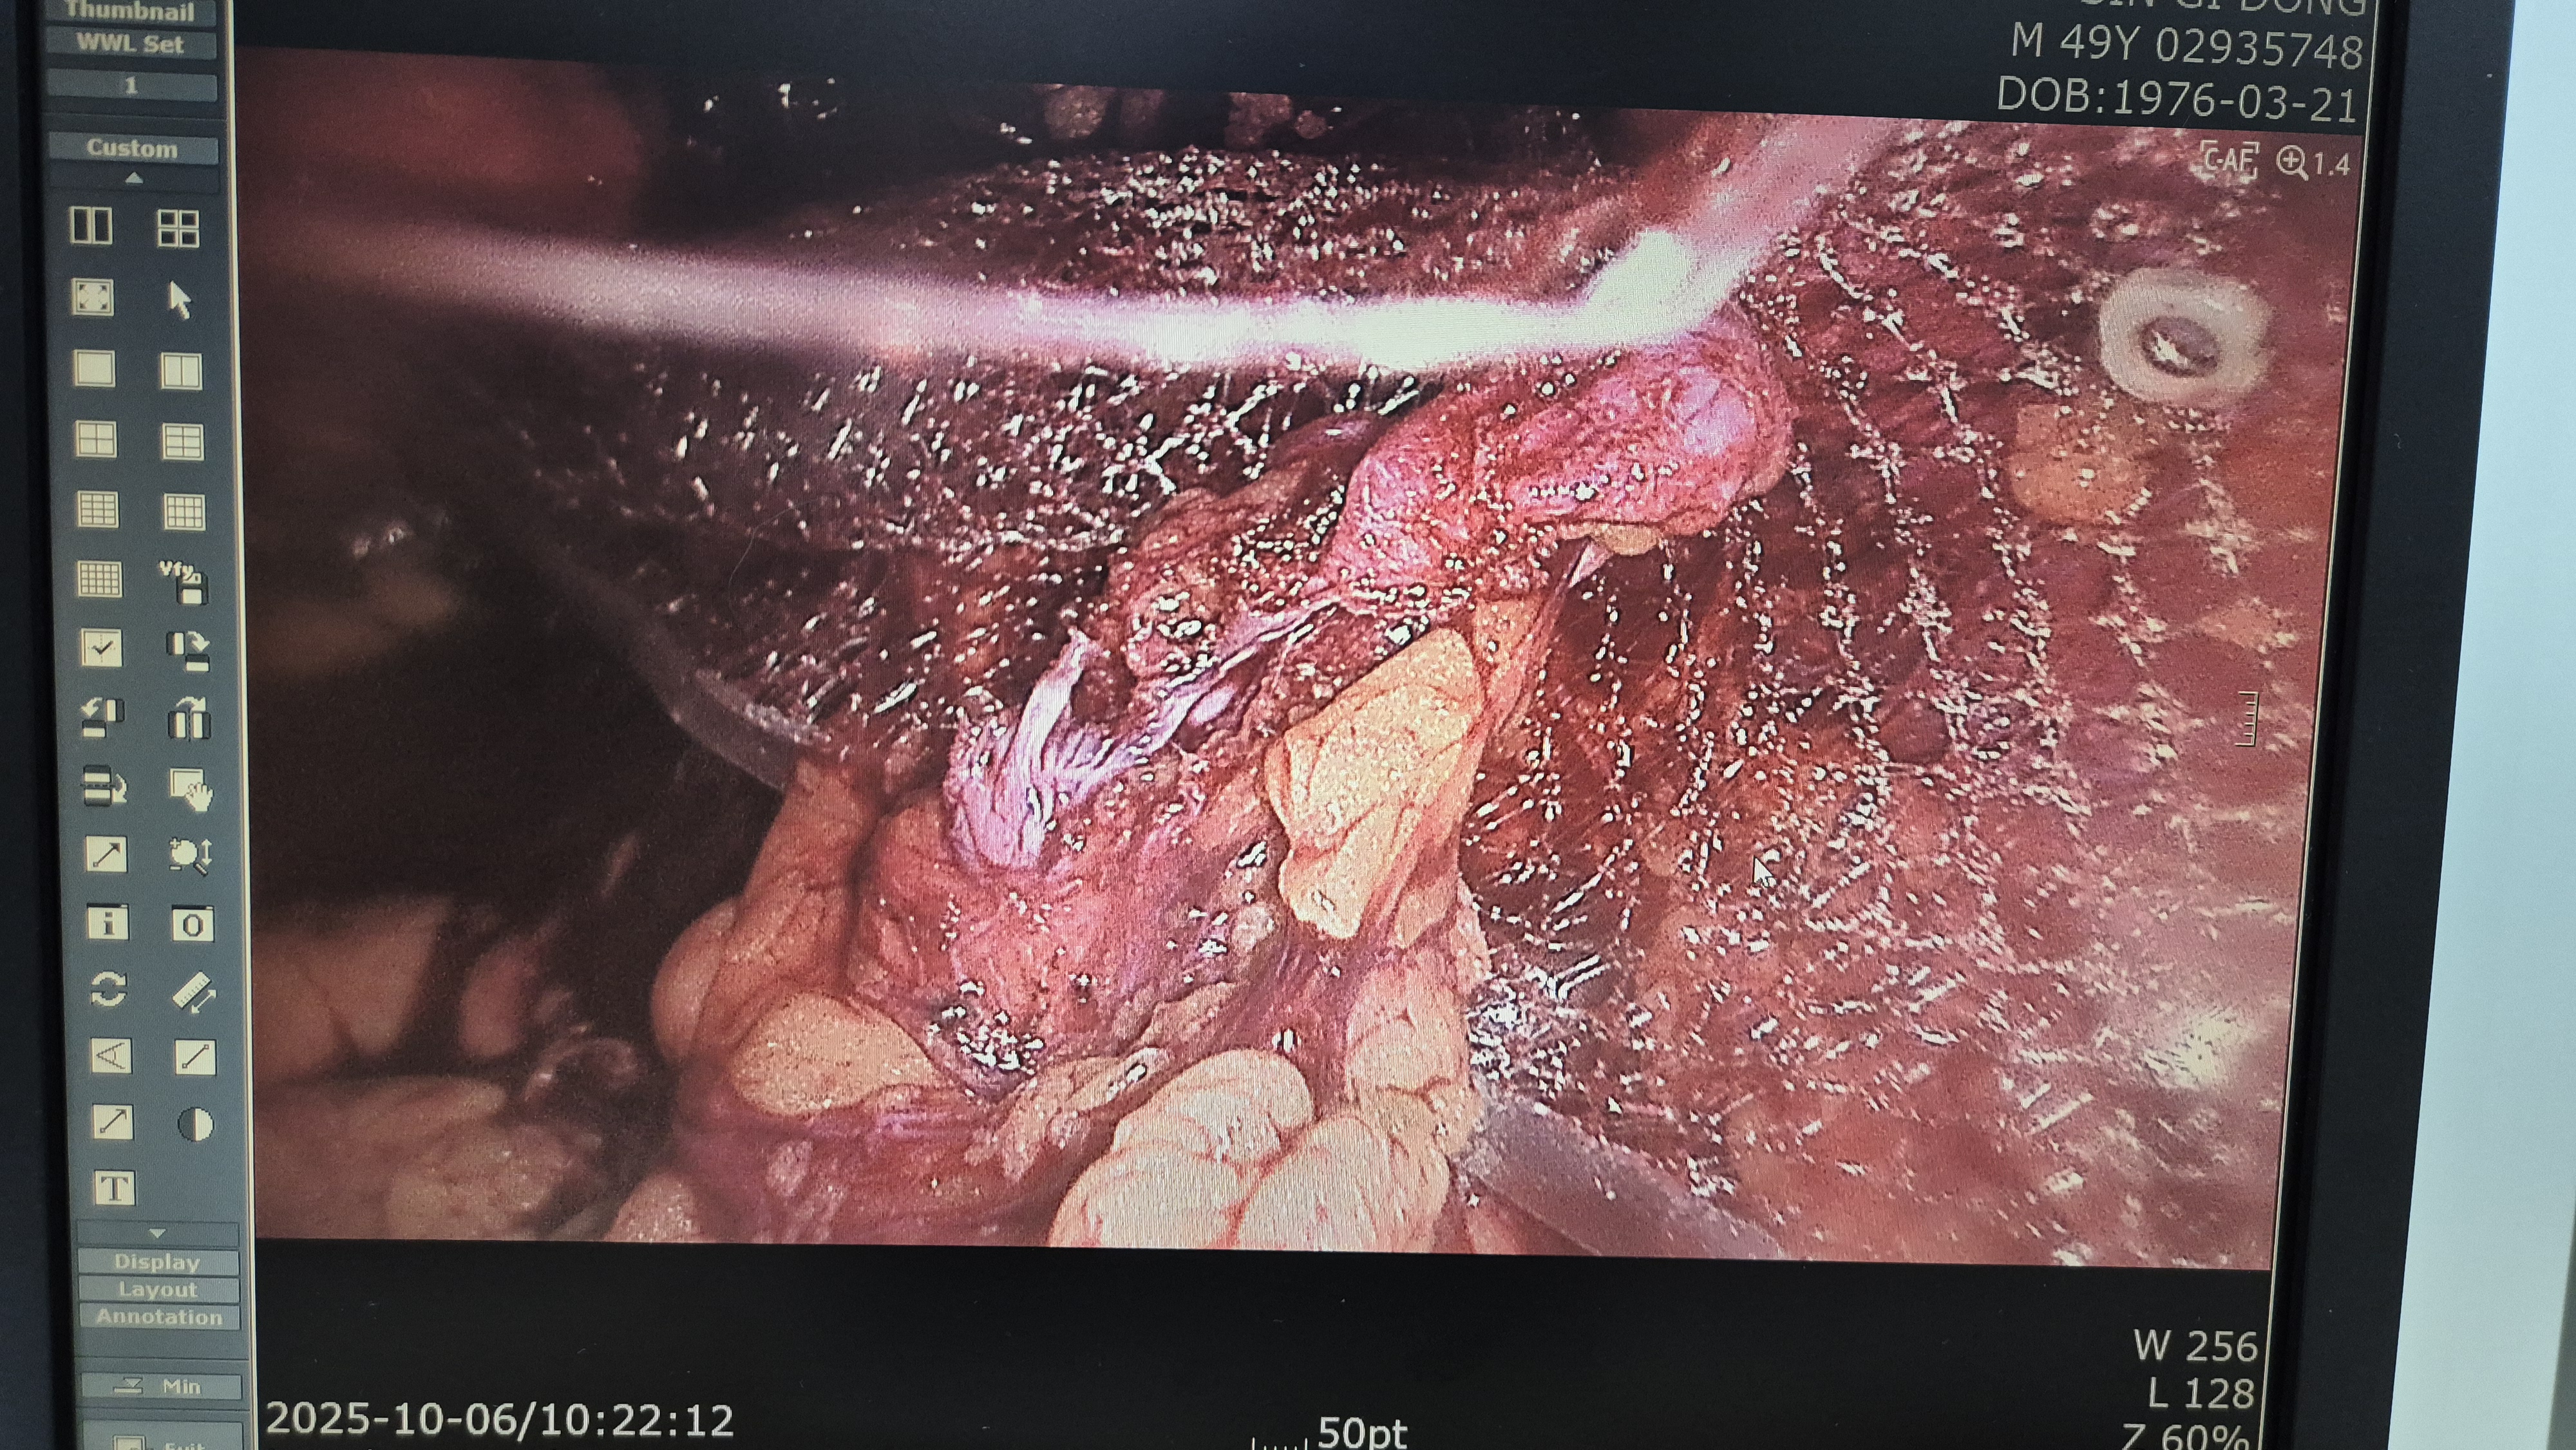

우측 서혜부 종물 주소로 내원하여 초음파 시행후 서혜부 탈장으로 확인되어,

방금 복강경 탈장교정술을 시행했습니다.

탈장 확인후.

박리.

메쉬로 고정.

수술은 15분 걸렸습니다.